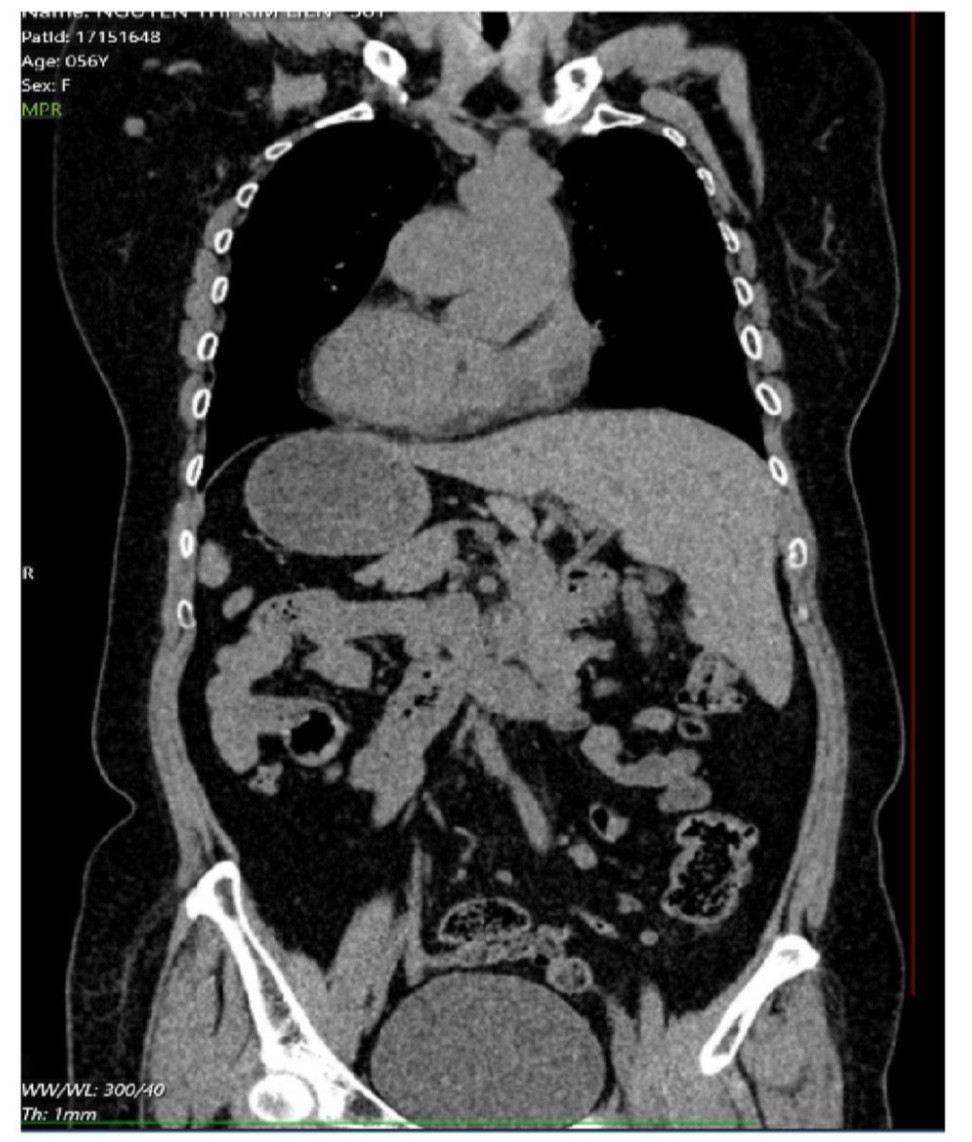

Bệnh nhân có phủ tạng đảo ngược hoàn toàn với trái tim nằm bên lồng ngực phải. Đây là dạng dị tật hiếm gặp, tỷ lệ 1/10.000 dân.

“Toàn bộ nội tạng của hai người bệnh có vị trí nghịch đảo, giống như hình ảnh soi gương của người bình thường: trái tim lệch sang phải, còn gan chuyển sang trái”, bác sĩ giải thích.